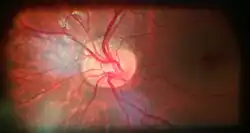

Almost all eye structures can be examined with appropriate optical equipment and lenses. Using a modern direct ophthalmoscope gives a view of the optic disc using the principle of reversibility of light. A slit lamp biomicroscopic examination along with an appropriate aspheric focusing lens (+66D, +78D or +90D) is required for a detailed stereoscopic view of the optic disc and structures inside the eye.

A biomicroscopic exam can indicate the health of the optic nerve. In particular, the eye care physician notes the colour, cupping size (as a cup-to-disc ratio), sharpness of edge, swelling, hemorrhages, notching in the optic disc and any other unusual anomalies. It is useful for finding evidence corroborating the diagnosis of glaucoma and other optic neuropathies, optic neuritis, anterior ischemic optic neuropathy or papilledema (i.e. optic disc swelling produced by raised intracranial pressure), and optic disc drusen.